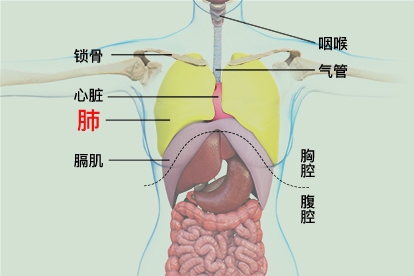

肺在人体的哪个位置图

(二)颜色肺位于胸腔内,纵隔两侧,因心位置偏左,故左肺狭长,右肺略宽短

发生在肺内的气体交换,第三章人体的呼吸,,肺的位置,,,位于胸腔内